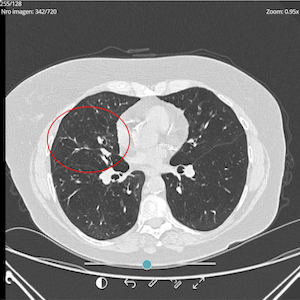

Clinical evaluation is complemented with Pulmonary function tests (Spirometry, lung diffusion, oximetry) and imaging (Chest X ray and CT scan).

PRE-TREATMENT

OCTOBER 2024

POST-TREATMENT

SEPTEMBER 2025